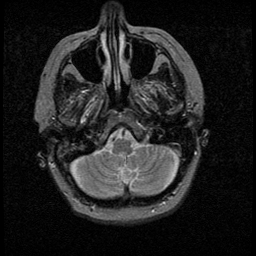

Huntington's Chorea, MR -- Slice #1

[Home][Help][Clinical] Slice 1